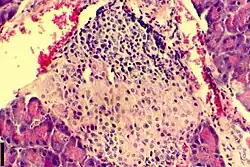

Insulitis

| A histological image of an inflammatory infiltration of the islets of Langerhans of the pancreas | |